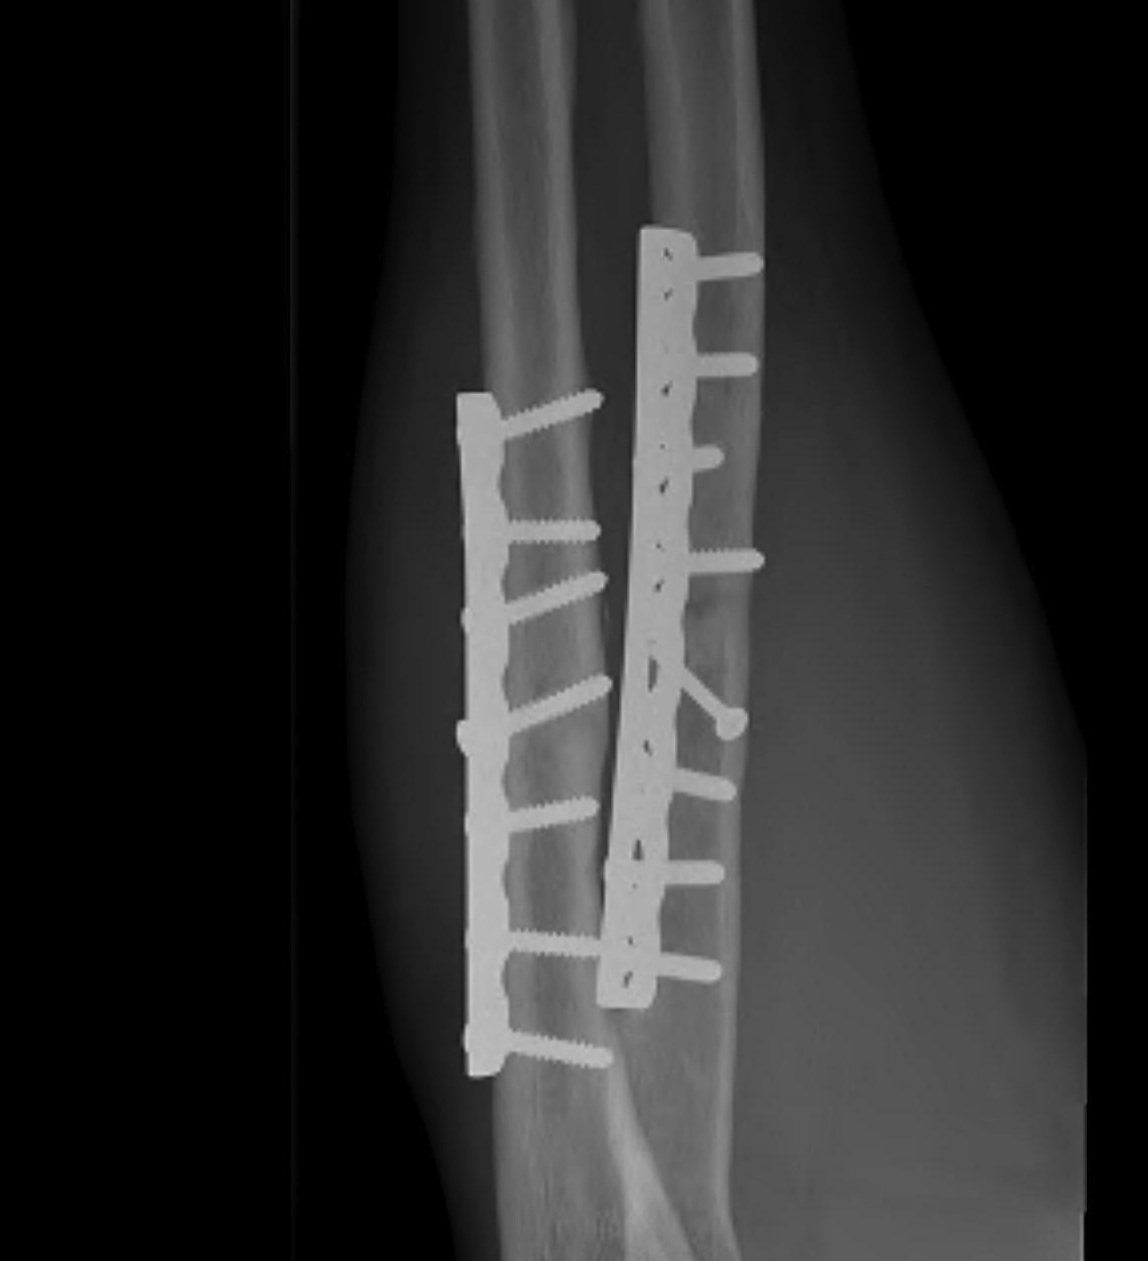

Plates

1. Neutralisation plate

2. Buttress plate

3. Tension Band plate

4. Bridging Plate

Bridging Plate

- used in the treatment of some multifragmentary fractures i.e. femur

- instead of individually fixing each fragment

- minimal disruption to blood supply

- reduction is performed indirectly

- compression is only sometimes possible

Concept

- 6 holes over each fragment if possible

- only fill 50% in intermediate fragments

- i.e. 3 bicortical screws sufficient

- near far near far concept